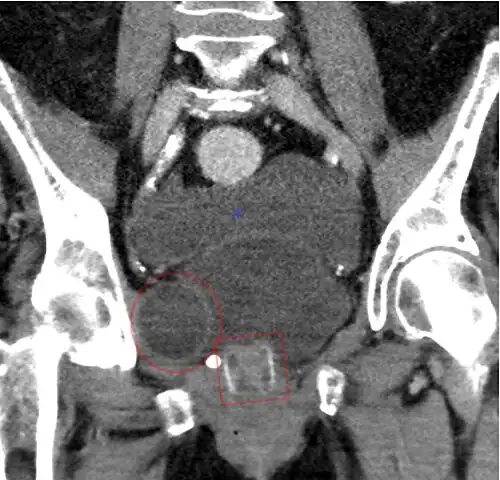

-

An X-ray image of implanted ZSI 375. The device is deactivated – the spring is compressed below the top of the cylinder. Patient is incontinent. -

An X-ray image of implanted ZSI 375. The device is activated – the spring is decompressed at the top of the cylinder. Patient is continent. -